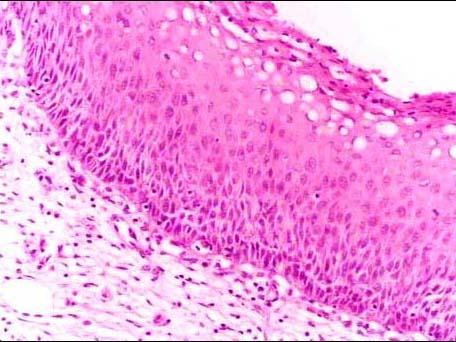

问题 女性,42岁,阴道接触性出血10天。宫颈活检镜下示鳞状上皮增生,部分细胞异型,局限在宫颈上皮层的下1/32/3(如图所示),正确的诊断是 ( )

选项 A.CINⅠ级 B.CINⅡ级 C.CINⅢ级 D.宫颈原位癌 E.宫颈鳞状上皮化生

答案 B